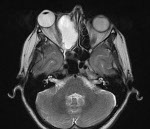

Рентгенологическое исследование при мукоцеле лобной пазухи определяет увеличение размеров пазухи, растяжение ее дна, уменьшение прозрачности. Возможно выпячивание перегородки между лобными пазухами в здоровую сторону. Прерывистость контуров лобной пазухи может указывать на наличие фистулы. Более точным и информативным исследованием является КТ лобной пазухи. Может применяться УЗИ и МРТ околоносовых пазух. В некоторых случаях для определения воздушности лобной пазухи проводится диафаноскопию. При затруднениях в диагностике мукоцеле лобной пазухи показана диагностическая пункция. Для определения проходимости лобно-носового канала производят зондирование лобной пазухи зондом Лансберга.